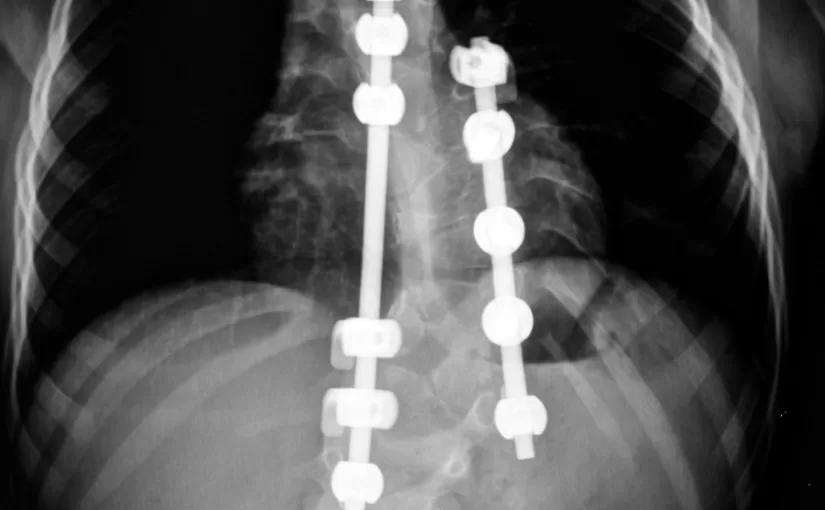

有时候治疗会使病情更糟糕 在这个10个小时的手术中,医生要将你身体的侧面和背面切开。在我特别的手术中,他们往我背里放三根钢筋,用五个螺丝钉将它们固定在一起,为了帮助我的骨头生长,他们取出我的一根肋骨和六个椎间盘,还从我的臀部(正在我屁股上)移植出一根骨头,拿走这根骨头 填上三个笼状物来支撑脊椎骨之间的那根骨头… 选自脊柱侧弯手术:Corey McConnell的经历 如果觉得听起来很可怕,记住,这可只是刚刚开始。对于青少年患者及其家长来说,脊椎矫正手术是一次很痛苦的经历。脊椎手术通常会牵涉大量组织和骨头创伤,产生的疼痛简直使患者难以忍受又不得不忍受。 更糟的是,尽管这样脊柱手术要耗费巨资,还并不一定保证能治愈,结果会不出所料。很多病例中,治疗之后比原本病情更加糟糕了。 那么为什么仍然有那么多的脊柱侧凸患者选择脊柱手术呢? 那个是很难回答的问题!对于这个问题我一直百思不其解,发现这么多年来,我们竟然离传统无手术的治疗模式这么久远了,我们已经忘记了在曾经没有医生挥舞手术刀的年代,仍然有那么多奇迹般的脊柱测凸康复患者。 这是我开始了一项深入的研究,在我最近几年治疗的上百个脊柱测弯患者的实践与经验中,我发现的确存在经得起时间考验的无手术脊柱侧凸治疗方法。 无手术脊柱侧凸矫正提供的是有效,安全和无痛的综合无手术治疗办法,可以治愈各种脊柱问题,如颈椎问题,腰痛,椎间盘突出等。 无手术脊柱测凸矫正技术吸收了来自世界各地最好的方案和办法,比如德国最早的Schroth疗法,以色列研发的Vertetrac系统,和美国用来治疗矫正脊柱侧凸,腰背疼痛,坐骨神经痛和疝气的震动疗法,物理疗法,具有令人鼓舞的效果。 无手术脊柱测弯矫正最大的优点就是除了无痛,更具成本效率(只需花费脊柱手术的一小部分),而且无副作用!唯一的要求就是,您必须承诺在一定时期内完成建议的运动和治疗方案,然后开始您的治疗。 无手术脊柱测弯治疗基本上包括: 营养疗法 民以食为天。大多数人深知,良好的营养与均衡的饮食是保证人体整体健康的重要组成部分。对于背部问题,可能令人讶异的是,饮食,营养和健康体重的保持都会对背部产生巨大作用,包括很多疾病的预防和创伤的愈合作用。脊椎中的骨骼,肌肉和其他结构需要良好的营养和维他命,这样才能足够强壮地支撑整个身体,发挥其他功能作用。通过营养指南,患者在饮食中加入有利于背部的维他命和营养品。 姿势和身体平衡训练 现在有大量关于门诊理疗,密集的住院康复治疗和矫正治疗的研究,这表明了脊柱侧凸治疗中锻炼的疗效。一个在土耳其的研究人员在沙特医疗学报上发表了一篇论文,论文内容关于Schroth的三度空间运动疗法——那是我在我的诊所用的青少年突发性脊柱侧凸的疗法——发现六周过去了,六个月过去了,一年过去了,这种疗法让所有患者的肌肉力量都在不断增长。而且,他们还报道,姿势缺陷也得到了显著改善。 脊椎按摩疗法 根据由脊椎按摩教育与研究基金会资助的一个耗时3年耗资143,000美元的研究成果显示,患有轻度脊柱测凸的儿童,用脊椎按摩疗法进行调整以后,发现他们的脊柱弯曲问题得到缓解 当务之急是,脊柱侧凸患者要得到一个训练有素的有良好脊椎治疗知识的理疗师的治疗。很多时候,未受过训练的手动理疗师只会试着拍拍打打把脊椎推回原来的位置。然而这种方法只对脊椎正常的人有作用,对于患有脊柱侧凸的病人没有作用,实际上反而可能加重脊柱测凸病情。 最先进的医疗设备 本诊所用到的几种最先进的医疗设备,即: 震动疗法 俄罗斯宇航员首次研究震动平台是用它在外层太空维持骨骼和肌肉质量。我首次更有效地运用震动疗法,是通过它对大脑控制肌肉的能力进行了再训练。当你站在震动机器上面时,你的姿势肌要进行多重快速调整——每秒多达50次,以适应相应的刺激来保持平衡。因此,如果锻炼和脊椎康复能结合震动疗法一起使用,效果是单独用他们治疗效果的3倍! Meditrac疗法 和Vertetrac疗法 这对L. Stabholz博士和A. Grober博士设计的传统牵引设备来说,是一个巨大的进步。这些医生发现,给患者抹上镇痛剂后(坐骨神经痛性脊椎测凸)对他们使用不同的牵引力有助于恢复正常直立的站姿,减少肌肉痉挛,通常可以痊愈。目前,本诊所在患者康复疗程中大规模运用Meditrac疗法 和Vertetrac疗法,加速血液循环到组织和椎间盘。 冲击波疗法 冲击波疗法指的是运用高强度的超声波辐射来治疗某些肌肉骨骼疾病。这种器械通过可以瓦解瘢痕组织和硬化部分的防护垫在创伤处集中高能量的声波,以改变组织结构,刺激骨骼生长,促进丢失组织的再生和体内钙的吸收,这些都能对脊柱侧凸的痊愈或部分康复大有好处。 无手术脊椎减压 这项由美国食品药物管理局批准的技术可以通过扩大椎间盘之间的空间来缓解疼痛。这种治疗方法已被认定为对严重的病情如疝气,病情恶化,关节炎,狭窄症和神经根压力有显著的疗效。据2004年骨科技术审查院完成的一项临床研究表明,所有的病历中,86%的患者通过使用椎间盘减压技术缓解了脊椎疼痛症状。 本人治疗脊柱侧凸患者的最佳时间是什么时候? 通常建设性的意见是,在它开始螺旋式失控以前,尽早矫正脊柱侧凸和任何背部问题。及时的治疗,我们可以将脊椎弯曲度减少到理想的5°或者更小,因此要彻底打败疾病而不只是将其制服。 唯一要牢记的是,相比手术只要在医院一天或两天就可以结束,接下来只是后期的锻炼康复工作,而我的治疗程序则需要更多坚持不懈的努力和专心致志的时间投入。优点便是,这明显比手术要省钱许多,也比手术更安全。 只要想想,在美国每年都有超过65万治疗背疼的外科手术,这每年需要超过100亿美元的花费。“这笔钱就不能花到更有用处的地方吗?”拉什骨科部前任主席安德森.贡纳尔博士问道。安德森博士和他的团队发现,人们的健康护理消费与他们的健康状况之间通常是没有联系的。这意味着我们总是把金钱花在并不必要的手术上了。 不要成为那个令人沮丧的统计数据中的一部分。